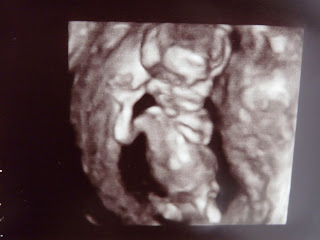

Toen nog even naar de baby gekeken en de hartslag beluisterd.

Ze vroeg of we het geslacht wilden weten?

Was echter een overbodige vraag zelf voor 2 leken als ons was het overduidelijk ....

Het wordt een jongen !!!!

Hoe grappig. Onze scampi lag mooi en ze kon alles heel goed opmeten. Scampi zat eigenlijk constant naar ons ze zwaaien. Zo lief :-)

Ze heeft zelf een 3D foto gemaakt omdat we zo lang hadden moeten wachten.

(13 weken zwanger 6,5 cm)